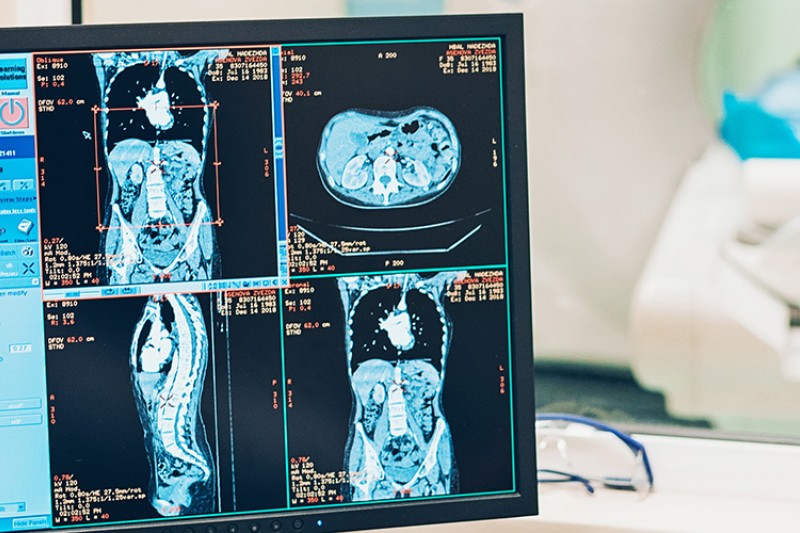

Our research strengths lie across a number of societally-driven areas – from helping people live better for longer, to protecting and preserving our environment, and supporting creative industries and cultural heritage to thrive.